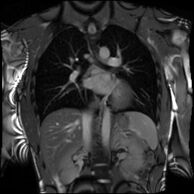

Partial Anomalous Pulmonary Venous Drainage by CMR